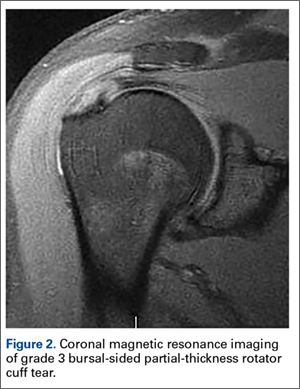

Figure 1: Rotator Cuff Tear This rotator cuff tear is seen in the The muscle is lit up in bright white and you can see a dark spot indicating the Figure 2: Partial Rupture This is a partial rupture of one of the rotator cuff The red arrow indicates the rupture Figure 3: Complete Rotator Cuff Tear